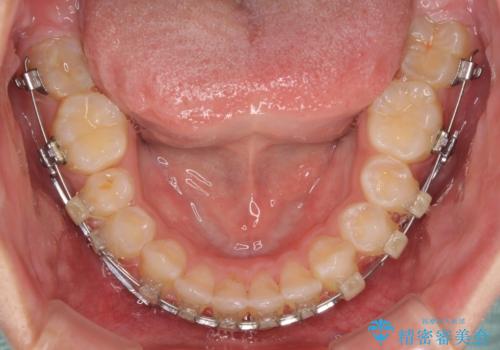

- クリアブラケット

下顎前歯が全て隠れてしまうほどの深い咬合で、左右の奥歯は1歯対1歯で咬み合う状態でした。

強く深い咬み合わせにより下顎装置は頻繁に脱離するため、治療期間が長くなりますが、予定通りに終了させることができました。